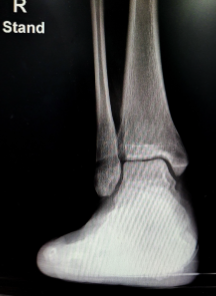

발목 인대파열 증상 수술 후 회복기간 등 인대에 관한 정보 알아보겠습니다. 발목 인대파열은 발목 관절을 구성하는 인대가 과도한 힘에 의해 늘어나거나 찢어지는 손상입니다. 발목 인대파열은 스포츠나 일상생활에서 자주 발생하는 부상입니다.

발목 인대파열의 치료방법은 손상의 정도와 개인의 상태에 따라 다르지만, 크게 수술적 치료와 비수술적 치료로 나눌 수 있습니다.

수술적 치료는 인대가 완전히 파열되었거나 보존적 치료로 회복이 어려운 경우에 시행합니다. 수술적 치료는 인대를 재결합하거나 인공인대로 대체하는 방법이 있으며, 수술 후에는 기브스로 고정하고 목발로 보행합니다. 수술적 치료의 회복기간은 약 6주 정도입니다.

비수술적 치료는 인대가 미세하게 파열되었거나 부분적으로 파열되었을 때 시행합니다. 비수술적 치료의 핵심은 RICE 치료라고 불리는 휴식, 냉찜질, 압박, 높이기입니다. 발목에 충분한 휴식을 취하고, 얼음으로 냉찜질을 한 후 붕대로 적절히 압박해 다친 부위를 심장보다 높은 위치로 유지하여 부종과 염증을 줄입니다. RICE 치료는 발목 인대파열 직후부터 가능한 한 빨리 시작하고, 2~3일 동안 반복합니다. RICE 치료 이후에는 보조기를 착용하거나 반깁스로 고정하여 발목 관절을 안정화시킵니다. 보조기나 반깁스를 착용하는 기간은 손상의 정도에 따라 다르지만, 일반적으로 2~3개월 정도입니다. 보조기나 반깁스를 착용하는 동안에는 재활 운동을 병행하여 발목 인대파열로 인해 손실된 근육과 관절의 기능을 회복시킵니다. 재활 운동은 도수치료나 물리치료와 같은 전문가의 지도 하에 진행하며, 발목의 구부림, 펴기, 내외회전 등의 운동을 합니다. 재활 운동은 통증이 완화되면 시작하며, 점진적으로 난이도와 강도를 높여갑니다. 발목 인대파열의 회복기간은 개인의 상태와 치료 방법에 따라 다르지만, 평균적으로 2~3개월 정도입니다.